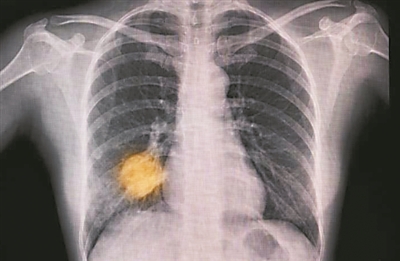

下图 人工智能工具的试验和两年一次的筛查有望帮助人们更早地发现肺癌。图片来源:《自然·医学》

人工智能在医疗领域的应用正从概念走向临床验证。MARS-ED临床试验旨在评估AI模型预测急诊患者短期死亡风险的能力,而另一项大规模试验则在测试AI通过胸部X光片实现肺癌早期诊断并分流患者的效能。这些研究对于推动AI工具从辅助决策走向可靠的临床实践至关重要。

在肿瘤领域,多项试验致力于优化诊疗策略。4-IN-THE-LUNG-RUN试验将评估两年期与一年期CT筛查在肺癌死亡率预防上的差异,旨在平衡筛查效益与医疗资源。此外,针对乳腺癌脑转移的德曲妥珠单抗(Enhertu)疗效验证,以及黑色素瘤新辅助免疫疗法(伊匹单抗联合纳武单抗)的NADINA试验,都代表了癌症个体化与综合治疗的新方向。